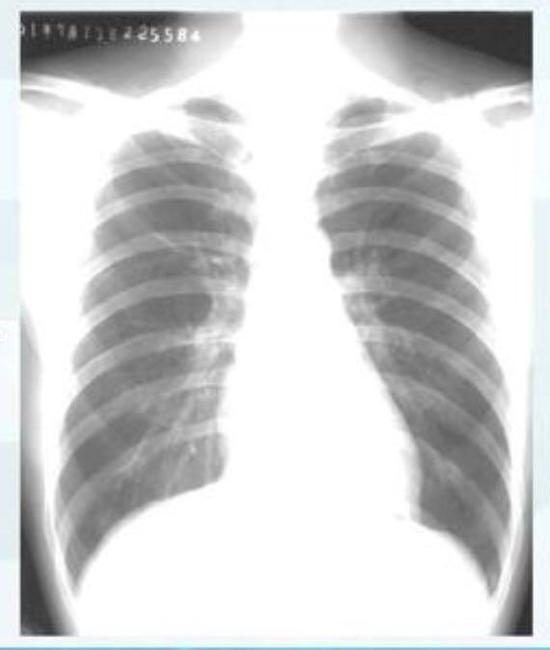

▲正常情况下人的肺部CT表现(图片来自网络)华中科技大学同济医学院协和医院研究者排除有严重呼吸窘迫和/或吸氧需求的患者,分析了21例轻度新冠肺炎患者的动态CT影像学资料。这些患者在平均(4±1)天内,共做了82次肺部CT扫描。学者发现,患者的肺部病变主要集中于肺下叶的胸膜下部位,从患者出现症状后约10 天,肺损害最严重,出现大片的白色致密“病灶”,约14天肺部病变开始改善直至吸收。